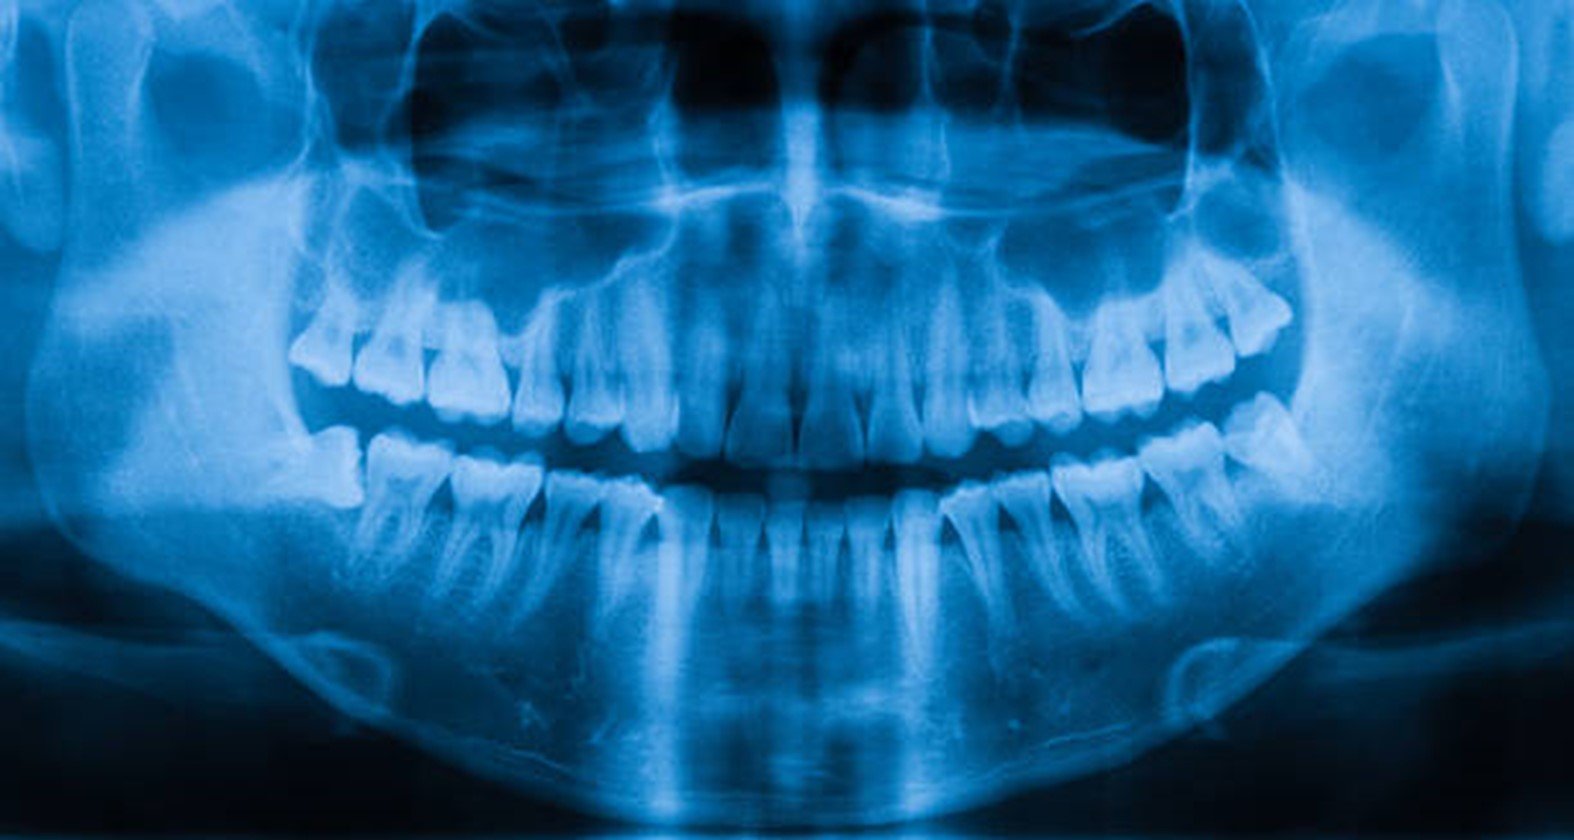

Saiba da importância da radiografia panorâmica

A radiografia panorâmica odontológica é a técnica radiográfica que permite a captura da mandíbula e do maxilar no mesmo quadro. Dessa forma, em uma única imagem, é possível observar todas as estruturas do complexo maxilomandibular, o que a torna útil em todas as especialidades odontológicas. Ela é a escolha ideal